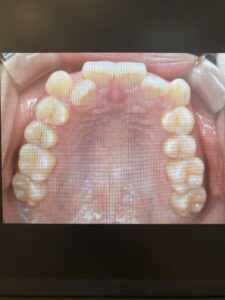

続いて、「iTero」という機械を用いて型取りをします。

しかし「iTero」は、この小さなカメラ(青い部分)を、お口の中で歯に沿わせて動かすだけで3Dのデータとして型取りすることができるので、型取りに苦手意識のある患者様の負担を軽減してくれます。

私は画面に表示されていく自分の歯型を横目に盗み見て感動していたら、苦しいと感じることもなくあっという間に終わりました。

「iTero」で撮影した3Dデータは、このように色々な角度から動かして見ることができるので、自分の歯はこんな形をしているのか!など新発見があるかもしれません。